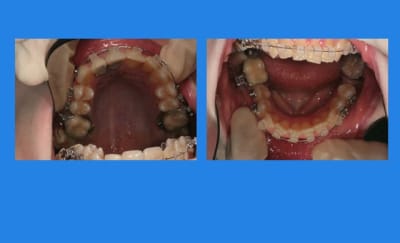

Début du cas :

pose mat Sup.

4mois après, comme ça n’avance pas vite, pose Q.H

et pose du mat. Inf.

contrôle 3 semaines après

Puis elle ne vient pas pendant plus de 2 mois

et, oh surprise (mauvaise)

c’est la cata !!!